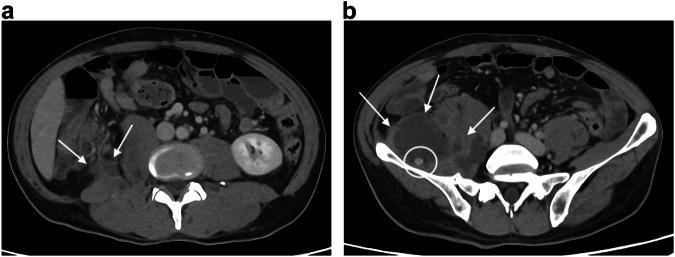

Abdominal disorders represent 10 to 15% of all Emergency Department visits in elderly patients. This educational review focuses on acute abdomen pathologies specific to the elderly and on their imaging patterns and proposes a strategy for performing CT scans in this population. Bowel obstruction is the most common cause of emergency surgery in the elderly with a higher proportion of colonic obstructions, in particular obstructive colorectal cancer and sigmoid volvulus. Concerning abdominal inflammatory processes, such as cholecystitis, appendicitis, and diverticulitis, gangrenous cholecystitis and complicated appendicitis are relatively frequently encountered due to delayed diagnoses. Bowel ischemia, which includes acute mesenteric ischemia (AMI) and ischemic colitis (IC), is also much more common after the age of 80. Although ischemic colitis is mainly related to cardiovascular risk factors, it can also result from a persistent distension above a colonic cancer or from fecal impaction. Finally, extra-abdominal pathologies responsible for acute abdominal pain, such as inferior myocardial infarction, should not be overlooked. In clinical practice, when possible thanks to sufficient and appropriate radiological resources, we recommend a scan without injection of contrast and an injection depending on the results of the unenhanced scan, decided by the radiologist present at the CT scan room during the examination. CRITICAL RELEVANCE STATEMENT: CT is critical in the diagnosis and management of patients over 75 years old with an acute abdomen, given the difficulty of clinico-biological diagnosis, the frequency of complicated forms, and the morbidity induced by delayed diagnosis. KEY POINTS: The most common site and cause of bowel obstruction in the elderly is large bowel obstruction due to colon cancer. Discrepancy between a poor clinical examination and complicated forms on imaging, particularly for inflammation and infections, is responsible for late diagnosis and increased morbidity. Ischemia, including of the small bowel, colon, and gallbladder are common cause of acute abdomen in elderly. In patients with upper quadrant pain, consider extra-abdominal causes such as pneumonia or myocardial infarction.

腹部疾病占老年患者急诊就诊总数的10%至15%。本教育综述聚焦于老年人特有的急腹症病理情况及其影像学表现模式,并提出针对该人群进行CT扫描的策略。肠梗阻是老年人急诊手术最常见的原因,其中结肠梗阻比例较高,尤其是梗阻性结直肠癌和乙状结肠扭转。关于腹部炎症性疾病,如胆囊炎、阑尾炎和憩室炎,由于诊断延误,坏疽性胆囊炎和复杂性阑尾炎相对较为常见。肠缺血,包括急性肠系膜缺血(AMI)和缺血性结肠炎(IC),在80岁以后也更为常见。虽然缺血性结肠炎主要与心血管危险因素有关,但也可能由结肠癌上方的持续性扩张或粪块嵌塞引起。最后,导致急性腹痛的腹外疾病,如心肌梗死,也不应被忽视。在临床实践中,若有足够且合适的放射学资源,我们建议先进行无对比剂注射的扫描,然后根据平扫结果由检查时在CT扫描室的放射科医生决定是否注射对比剂。关键相关性声明:鉴于临床生物学诊断困难、复杂形式的发生率以及延迟诊断导致的发病率,CT对75岁以上急腹症患者的诊断和管理至关重要。关键点:老年人肠梗阻最常见的部位和原因是结肠癌导致的大肠梗阻。临床检查结果不佳与影像学复杂表现之间的差异,尤其是对于炎症和感染,导致诊断延迟和发病率增加。缺血,包括小肠、结肠和胆囊缺血,是老年人急腹症的常见原因。对于上腹部疼痛的患者,应考虑腹外原因,如肺炎或心肌梗死。